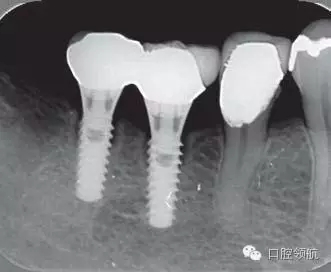

2005年4月時,可見(左下第6顆牙) 部的種植體達(dá)到第4螺紋,(左下第7顆牙)的種植體周圍觀察到位于第3螺紋的頸部進(jìn)行性骨吸收(圖4)。到2009年9月時,骨吸收像的周圍有了明顯的骨密度增加影像(圖5)。

圖4 (左下第6顆牙)的種植體達(dá)到第4螺紋, 7 的種植體達(dá)到第3螺紋的頸部進(jìn)行性骨吸收現(xiàn)象(2005年4月)。